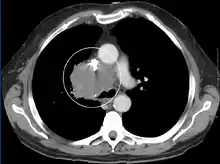

CT 扫描应进行对比增强,并针对颈部、胸部、下腹部和骨盆进行。 [5]它们还可能显示根本原因以及疾病进展的程度。 [5]